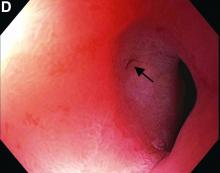

Question: A 74-year-old man with a history of Helicobacter pylori–related prepyloric ulcer (Figure A) resulting in pyloric stenosis (Figure B) and gastric outlet obstruction, now presents to the clinic with recurrent nausea, vomiting, and weight loss for the past 2 months. Two years ago, the patient had similar symptoms, which required 2 endoscopic dilations and continued course of proton pump inhibitors. Since then, the patient was lost to follow-up and is now returning to the clinic. On physical examination the patient is cachectic and nonjaundiced and has mild epigastric tenderness and a scaphoid abdomen. The patient’s hemoglobin is chronically stable at 12.5 g/dL (normal range, 13.5-17.5 g/dL) and other relevant laboratory results are within normal limits. Upon endoscopic examination, the patient is found to have recurrent pyloric stenosis, gastric outlet obstruction with significant amount of retained food, and a healed prepyloric ulcer. Standard as well as thin caliber endoscopes were unable to pass through the pyloric stenosis. Consequently, a guidewire was inserted into the pyloric opening to perform over-the-wire balloon dilation of pyloric stenosis under fluoroscopy. Contrast was injected to confirm luminal positioning of the balloon and findings in Figure C (arrow) were obtained.

This patient has a known history of prepyloric peptic ulcer disease and related gastric outlet obstruction requiring two previous dilations. Upon endoscopic examination, we observed high-grade obstruction at the pylorus similar to previous examinations. During the initial positioning of the balloon for dilation, we inadvertently cannulated the fistula located in the pyloric channel using the guidewire (arrow in Figure D) and were able to characterize its anatomy upon contrast administration (Figure C). However, after repositioning the guidewire into the duodenal lumen beyond pyloric stricture, the balloon was inflated to a maximal diameter of 15 mm under fluoroscopic guidance. Discounting other common causes, our patient presented with an infrequent occurrence of choledocopyloric fistula secondary to peptic ulcer disease.